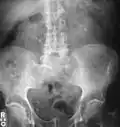

Calcium-containing stones are relatively radiodense (opaque to X-rays), and they can often be detected by a traditional radiography of the abdomen that includes the kidneys, ureters, and bladder (KUB film).[59] KUB radiography, although useful in monitoring size of stone or passage of stone in stone formers, might not be useful in the acute setting due to low sensitivity.[60] Some 60% of all renal stones are radiopaque.[61][62] In general, calcium phosphate stones have the greatest density, followed by calcium oxalate and magnesium ammonium phosphate stones. Cystine calculi are only faintly radiodense, while uric acid stones are usually entirely radiolucent.[63]

Bilateral kidney stones can be seen on this KUB radiograph. There are phleboliths in the pelvis, which can be misinterpreted as bladder stones. -